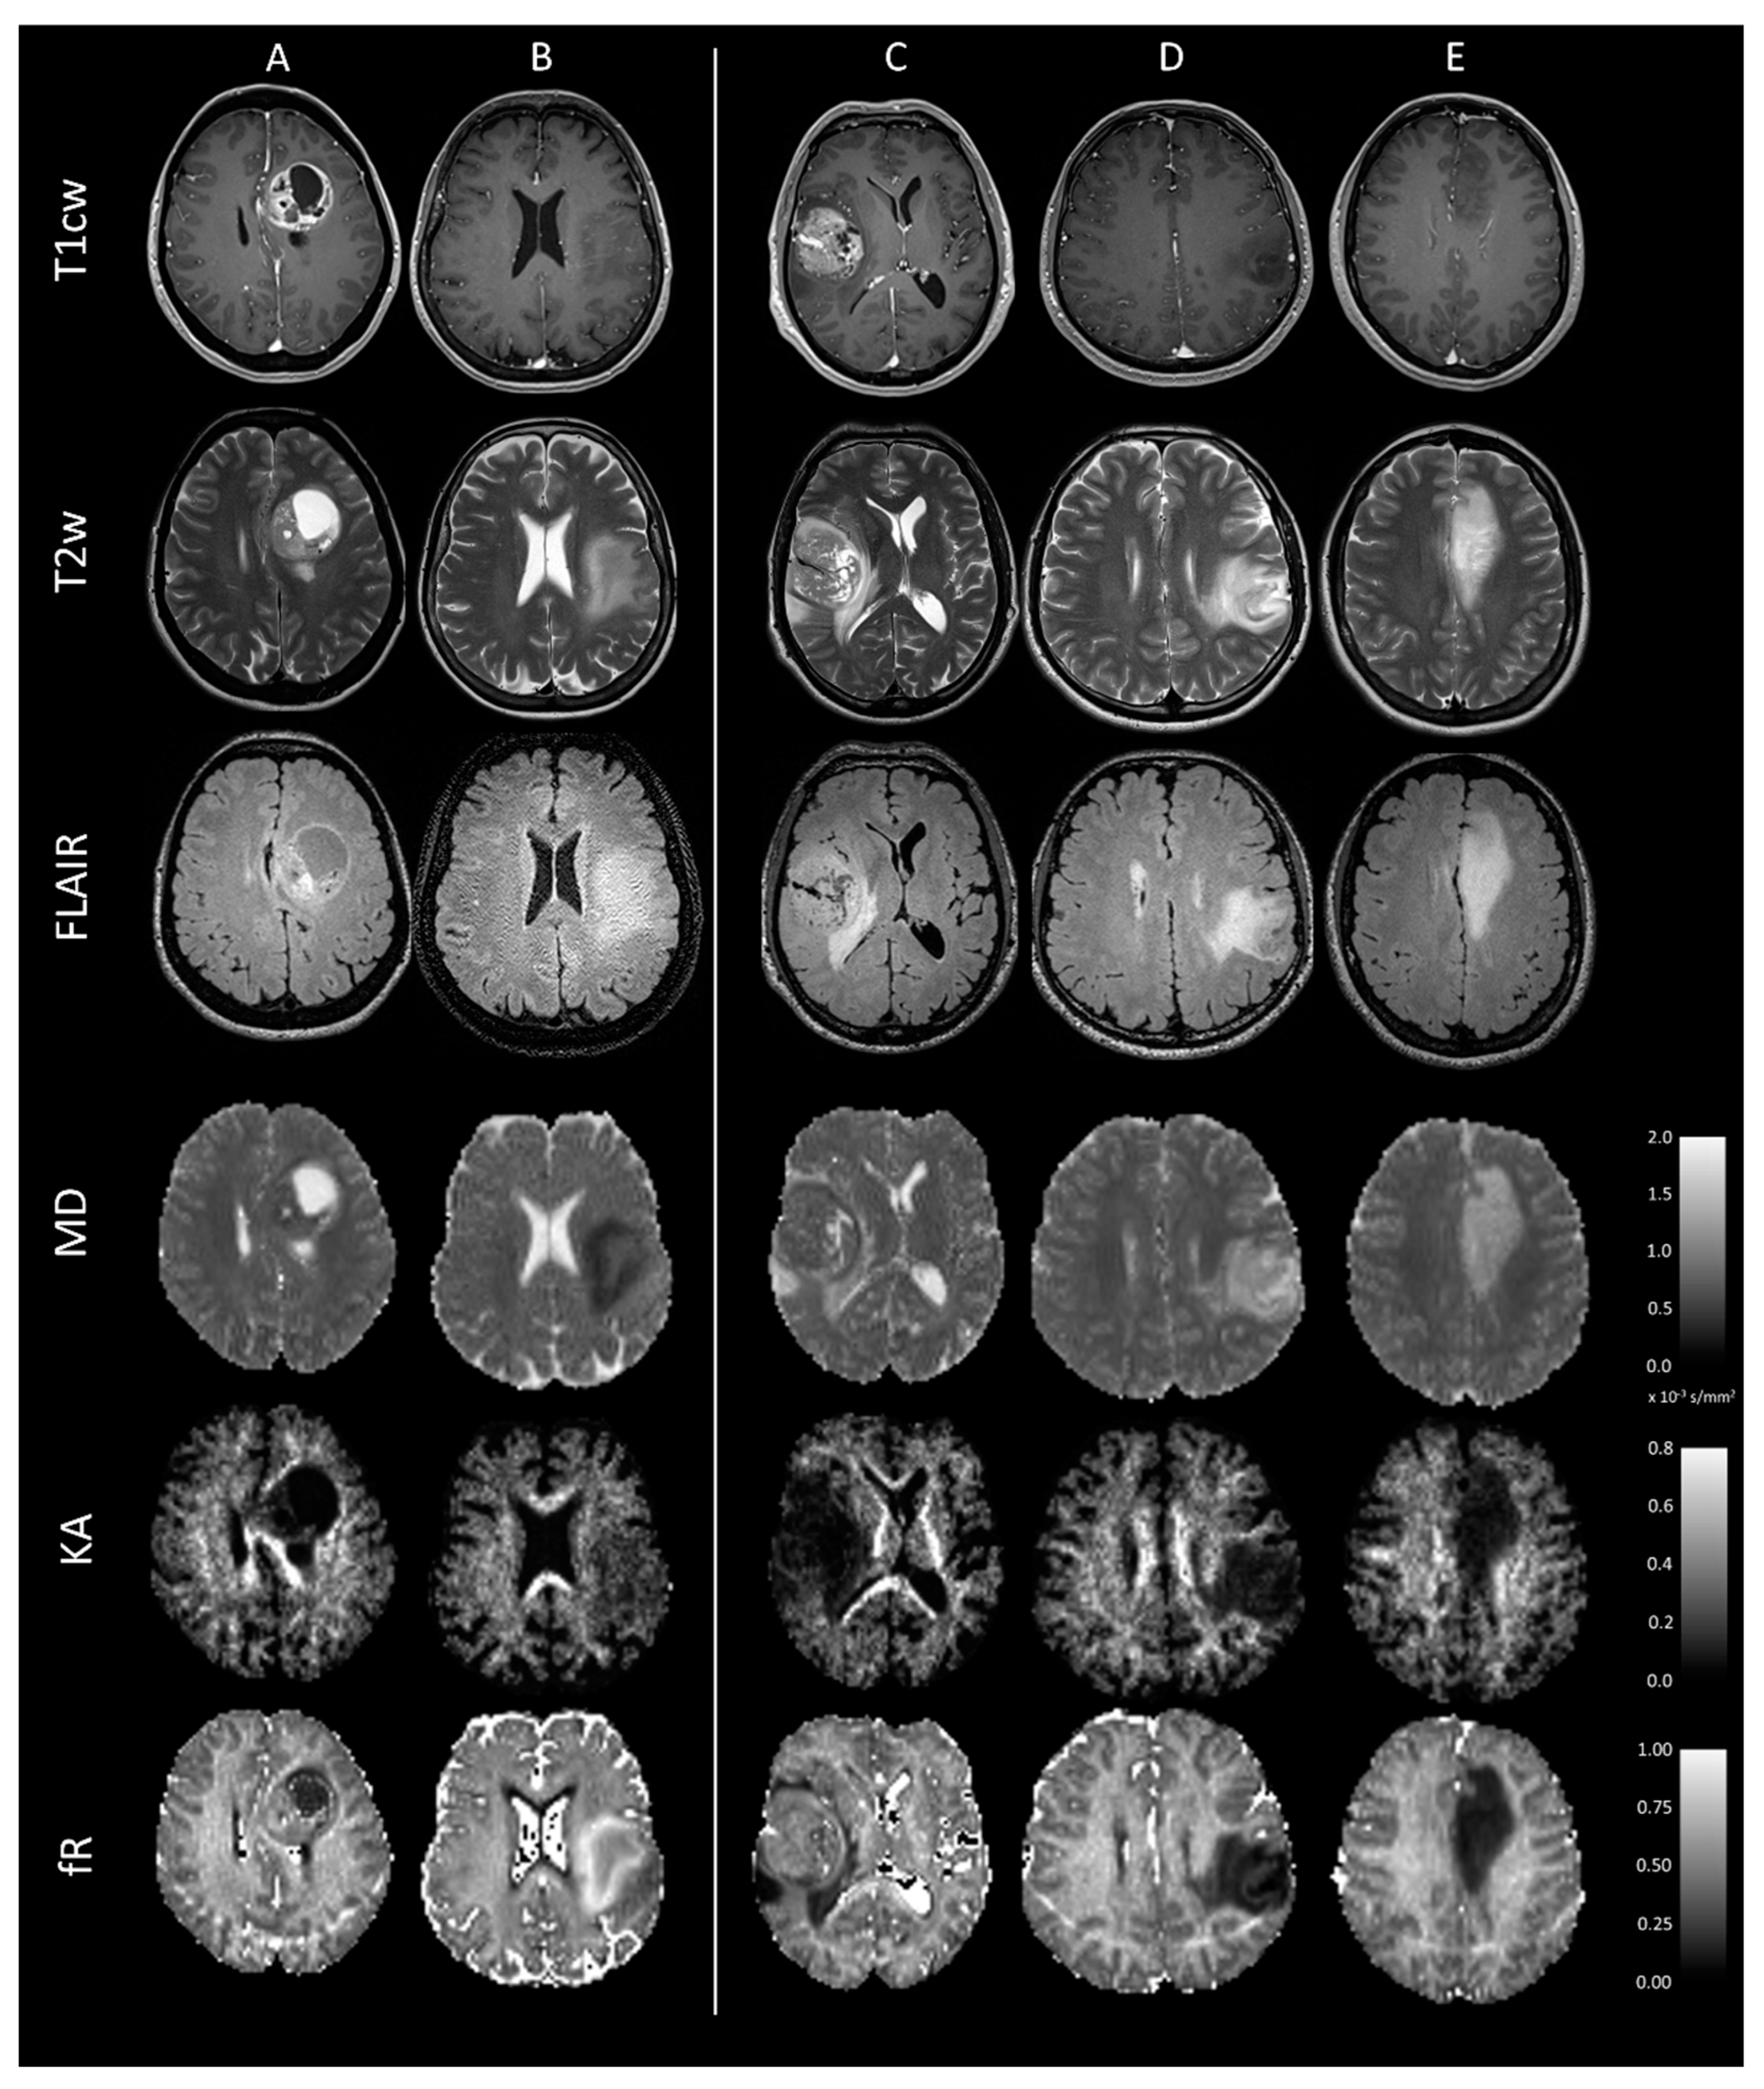

2.3. Image Acquisition and Processing

2.4. Input Data